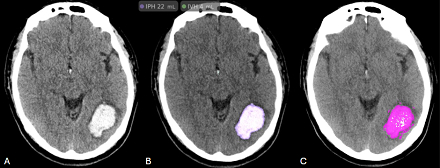

Reliability and Agreement of Artificial Intelligence and Semi-Autonomous Quantification of Anticoagulant-Related Supratentorial Intraparenchymal Hemorrhage

FDA clearance of fully automated artificial intelligence (AI)-based software for quantifying intracerebral hemorrhage (ICH) volumes has the potential to meaningfully impact the acute management of hemorrhagic stroke. ICH volume is a critical prognostic factor, with larger hemorrhages associated with oral anticoagulant (OAC) use typically resulting in poorer outcomes. Quantifying ICH volume in OAC-related ICH presents challenges due to variability of morphology and density. Although prior studies suggest AI models may improve the accuracy of ICH volume calculation compared to the ABC/2 method and Semi-Autonomous Segmentation (SAS), there is limited data evaluating their performance in OAC-related ICH.

A retrospective analysis was conducted on 161 adults presenting to a comprehensive stroke center from 2016-2021 with acute supratentorial OAC-related ICH. Volumes on initial de-identified CT brain were measured using SAS (Syngo.Via, Siemens) and AI (Viz ICH volume, Viz.ai). Agreement of ICH volumes between SAS and AI was assessed using the Intraclass Correlation Coefficient (ICC) for absolute agreement. A two-way mixed effects model was employed for single measurements. A Bland-Altman (BA) analysis with proportional bias assessment was performed. Data analysis was conducted using R studio.

Out of 161 adults, 50 met eligibility criteria and 39 (78%) CT scans were analyzed by AI and SAS. AI software failed to correctly process 11 scans due to small ICH volumes (n=8), misclassification of lesions as subdural (n=1), or image retrieval issues (n=2). For the 39 scans that were analyzed, the median ICH volume measured by SAS was 15.89 cm3 (IQR 5.69 – 41.86 cm3) and by AI was 17.0 cm3 (IQR 5.0 – 44.5 cm3). The ICC for absolute agreement between the software platforms was 0.973 (95% CI 0.950 – 0.986), indicating excellent reliability. A BA plot revealed a mean difference (bias) of -0.861 cm3 (95% CI -3.1 – 1.37 cm3) with limits of agreement from -14.84 cm3 to 13.12 cm3, demonstrating good agreement between the two methods with no significant proportional bias.

There is strong agreement and reliability in OAC-related ICH volume measurements between SAS and AI. Such local validation is imperative for safe and responsible integration of AI tools into clinical workflows. Further research into limitations of AI, including failure modes and biases is necessary to inform human oversight.